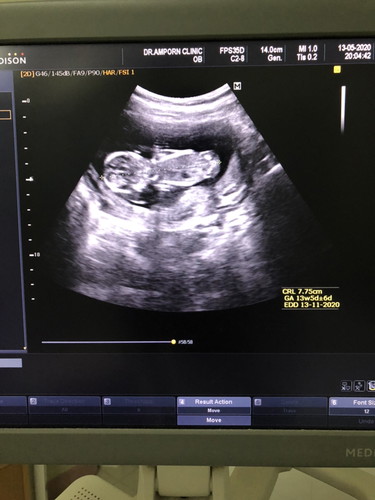

12wจ้า 6 cm กว่าๆ ดีใจเหมือนกันค่ะคุณแม่ น้องเกิดเดือนธันวาใช่ไม๊ ดีใจด้วยนะคะ คุณแม่ดูแลสุขภาพดีๆเด้อ

บ้านนี้ 14 w 9.25 ซม. ให้โชคแม่จ๋าด้วย 😊😊

ดีใจด้วยจ้า ของเรา12วีค 5 เซ็นเอง